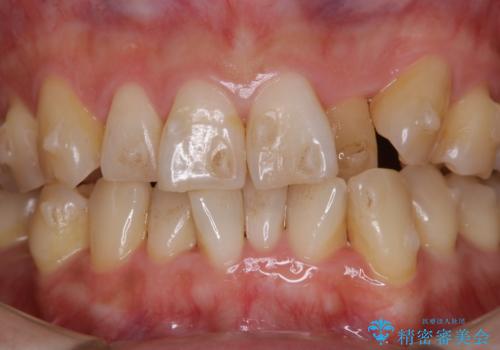

インビザラインでのマウスピース矯正中に歯を白くしたい

- インビザラインでのマウスピース矯正中に、歯の黄ばみが気になるため綺麗に白くしたいとのことでした。PMTC60分コースを行いました。

PMTC(保険外治療)は、毎日の歯磨きで落としきれない汚れや、コーヒ、紅茶・タバコのヤニなどの着色も除去します。目には見えない歯と歯の間・歯肉の境目・インビザライン中はアタッチメント周囲などに残っているプラーク(歯垢)もしっかり取り除きます。PMTCでは専門的な機械や材料を使用して、徹底的に汚れを除去するため、虫歯・歯周病・口臭予防などにつながります。

またPMTCを行うことで、ご自身本来の歯の色になり自然な明るさになります。